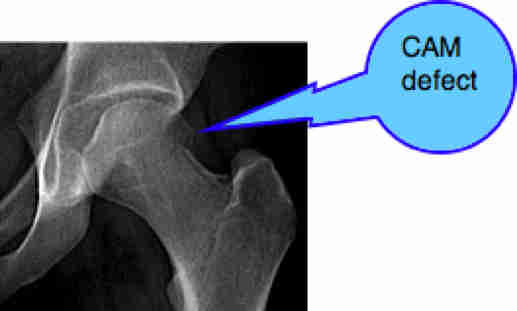

FEMORO ACETABULAR IMPINGEMENT SYNDROME

FAIS comes in two forms. CAM and Pincer. Most people suffering from the condition actually have both, but she has only the CAM deformity. As if that wasn't enough: groin pain. Very treatable with Chiropractic help.

The answer to my initial question? In my opinion the primary is in the hip. That's what set up her lower back pain. For another, more detailed and interesting case, see our Chiropractic Help newsletter # 31. See the bottom of this page.

My own interest currently is how Chiropractic can help joints outside of the spine. By applying the same principles that we use with the spine, I'm getting very good results with hips right now, for example. The hip is prone to two conditions: too much cover, Femoro Acetabular Impingement Syndrome, and too little cover of the ball (Hip Dysplasia) both of which offer much challenge to the clinician. Pain in the groin is the hallmark. Untreated, both prematurely become arthritic.